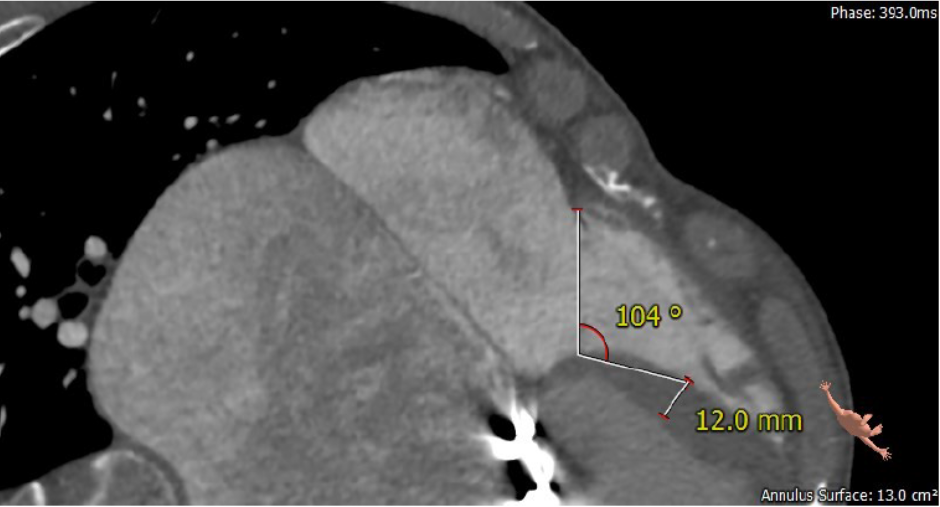

第二例患者为56岁男性,25年前接受了“主动脉瓣+二尖瓣机械瓣置换术”,约18年前出现三尖瓣关闭不全,近年来复查彩超示三尖瓣反流逐渐加重伴轻微黄疸、双下肢水肿,虽长期服用利尿剂治疗,但效果越来越差。长海医院心外科徐志云、陆方林团队综合该患者CT、超声检查结果,对该患者的情况进行了充分的评估和讨论,决定采用LuX-Valve®瓣膜系统对患者进行微创治疗。手术于7月12日下午进行,由于病人左心房扩大压迫右心房,心室游离壁距离瓣环中心仅29.8mm,再加上室间隔与瓣环夹角过大,手术操作有一定难度,瓣膜锚定也需要相当的经验。

根据术前CT的测量结果,选择使用JS/TTVI-28-40型号的LuX-Valve®瓣膜。陆方林教授用导管顺利将介入瓣送入右心室,过三尖瓣瓣环到达右心室,精准地控制着输送系统,最终和超声确认无瓣周漏后对瓣膜进行锚定,术后超声和造影显示瓣膜位置良好,几乎无反流。